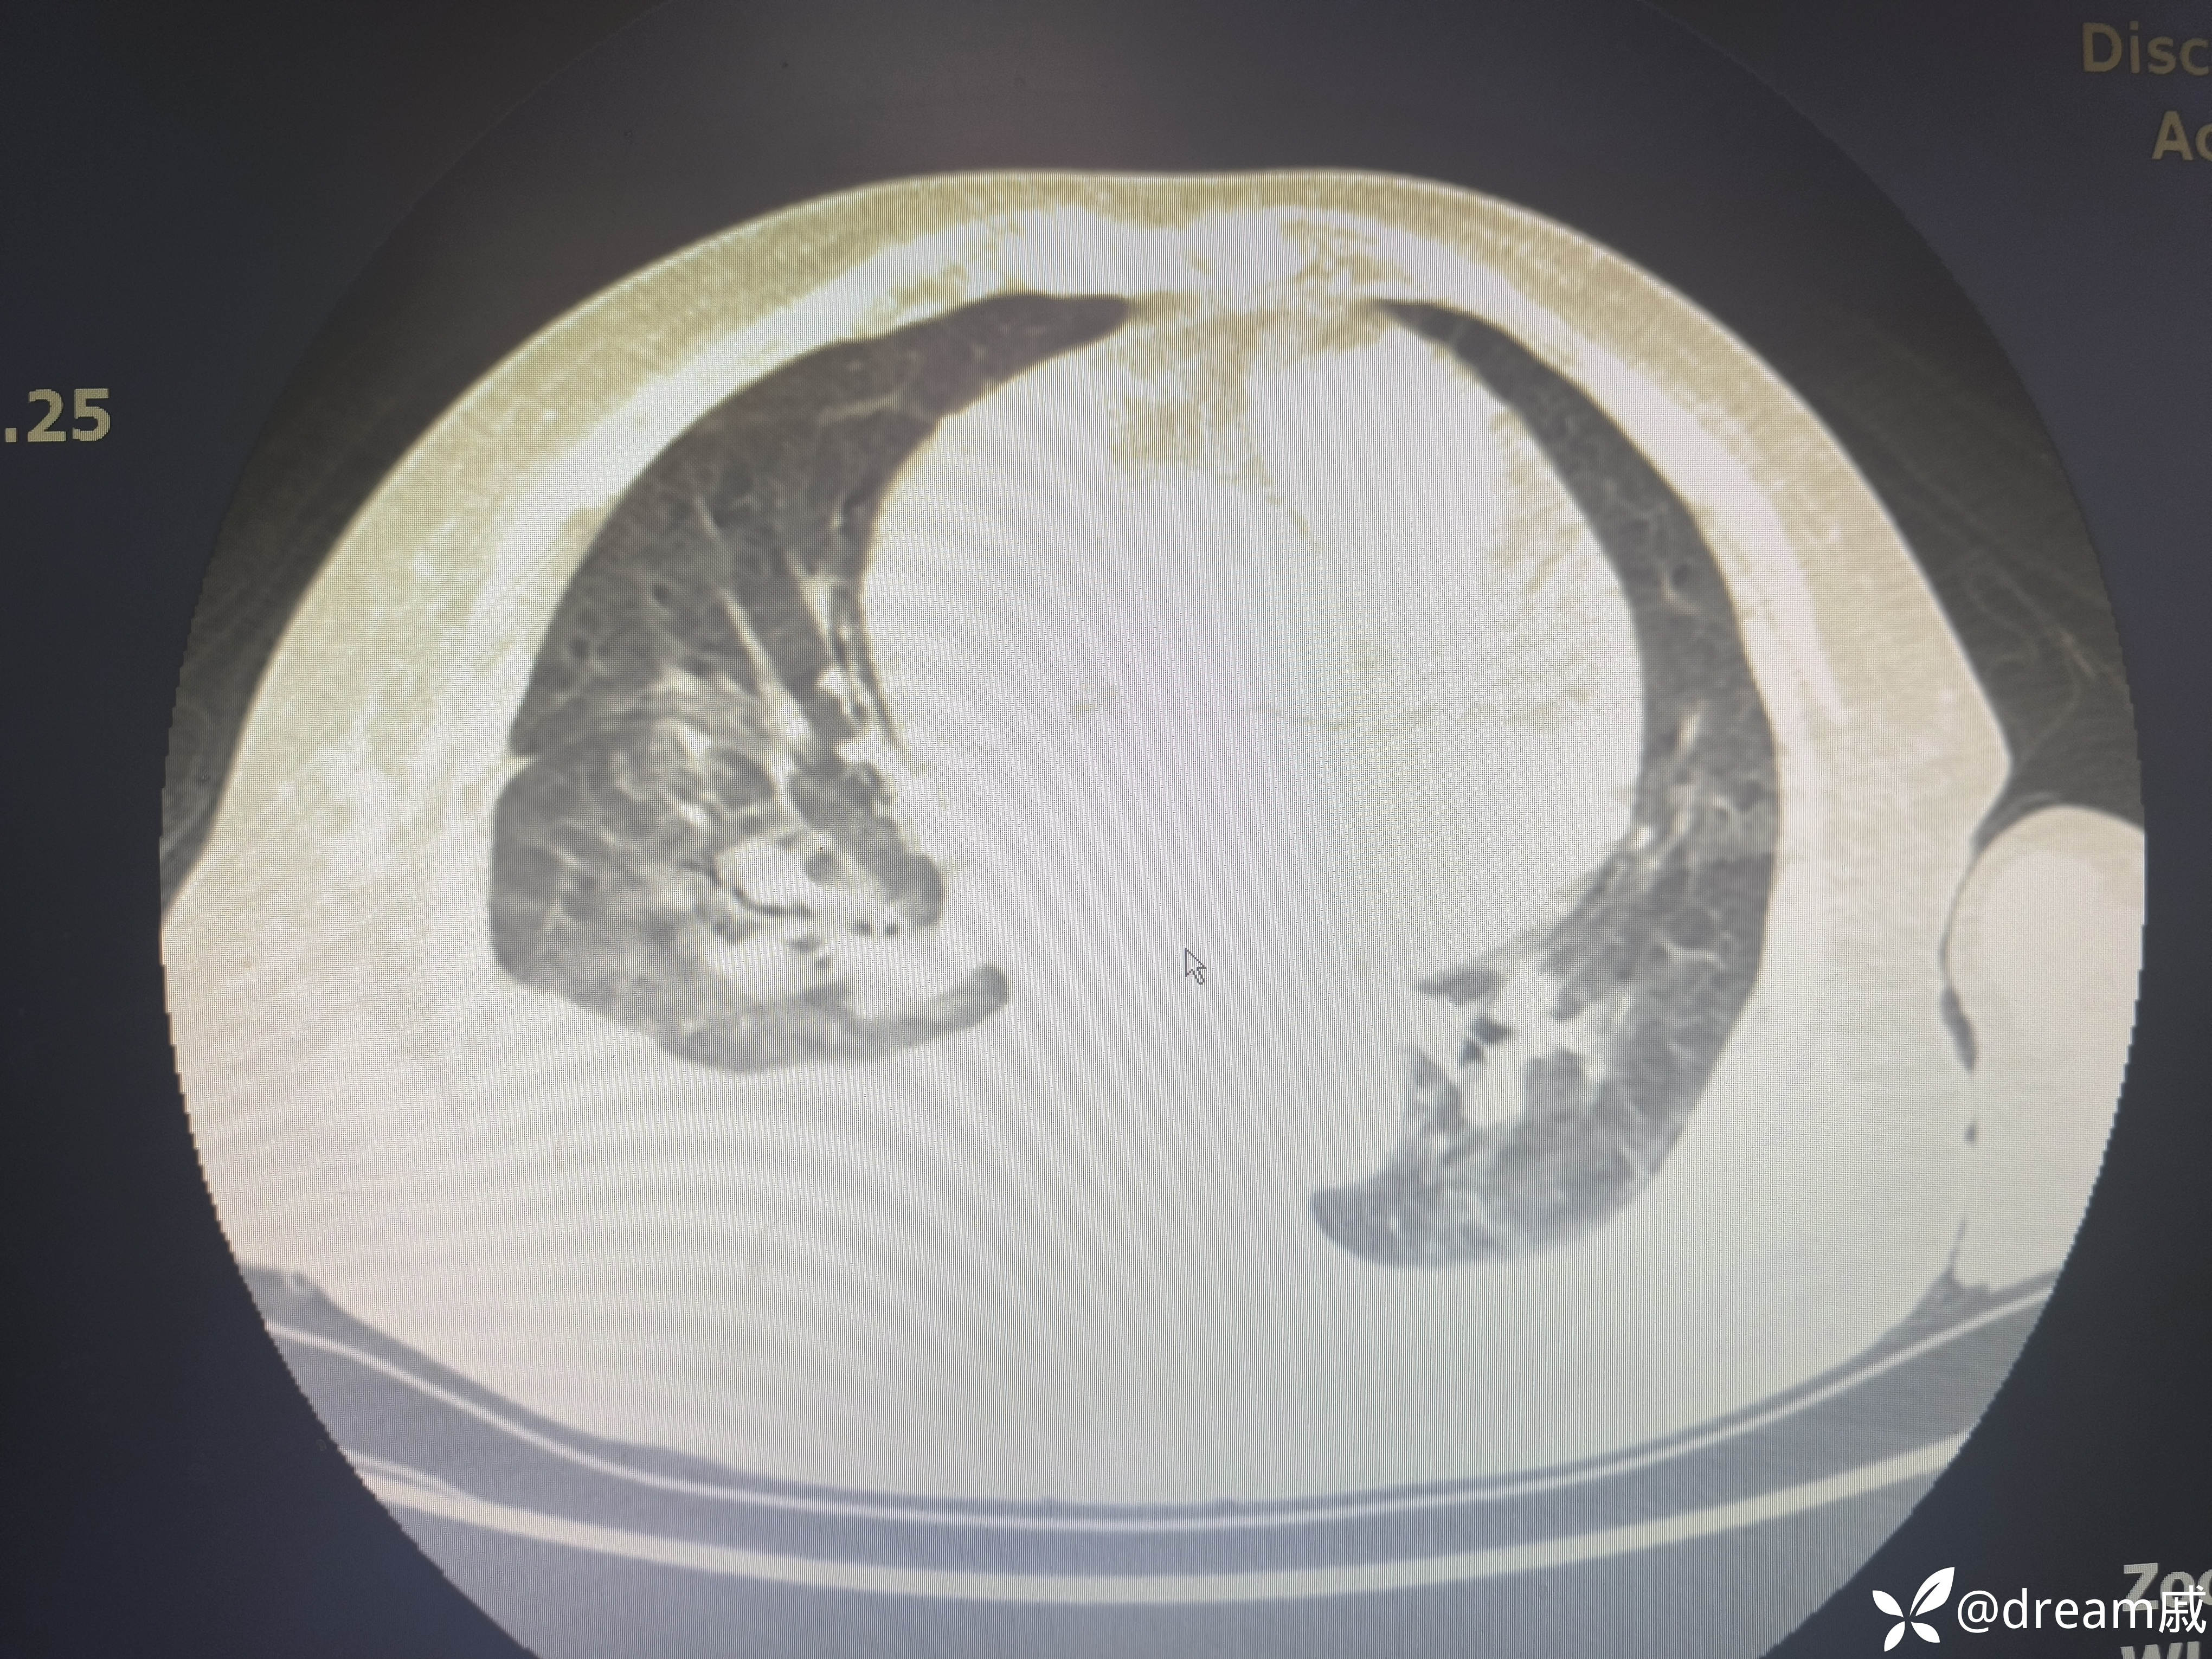

胸部CT示右肺中下叶斑片影,双肺局部间质性改变。

5月27日复查CT如下